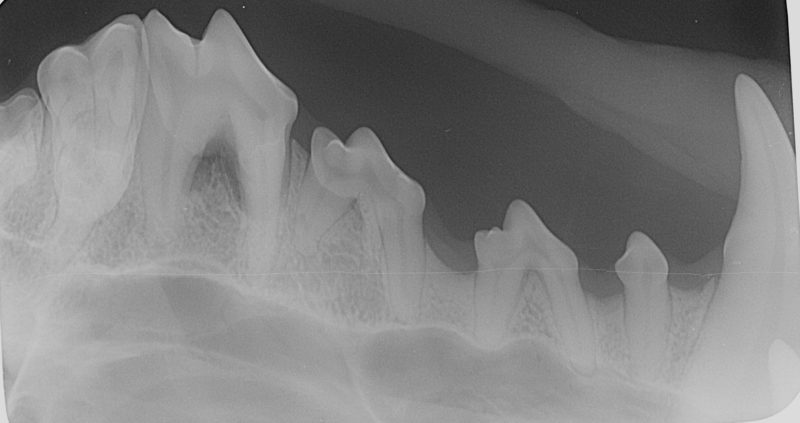

Für eine ordentliche Narkose wird standardmäßig die Inhalationsnarkose durchgeführt. Nachdem „Alyza“ intubiert wurde, wurden die Zähne geröntgt. Die Röntgenbilder zeigen eine deutliche Reduktion des Knochens. Die Zähne wurden von dem Belag befreit, die Zahnfleischtaschen mit Paradontalsonde untersucht. Die Befunde sprechen für beidseitige Paradontose der oberen vierten Prämolare (Backenzähne im Gebiss von Säugetieren). Die Zähne haben ihre Bezeichnungen bzw. Nummern. Diese Zähne heißen P4, genauer haben sie Nummern „108 und 208“, wo 1 für rechts oben, und 2 für links oben steht, und Nummer 8 ist die Zahnnummer auf der entsprechenden Seite.